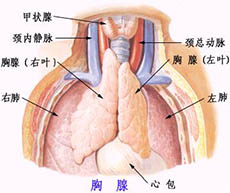

先天性甲状腺功能减低症

疾病介绍:先天性甲状腺功能减低症(简称甲低)又称克汀病或呆小病,多见于先天甲状腺缺陷,主要表现为体格和精神发育障碍,早期诊断和治疗可防止症状的发生或发展…【详细】